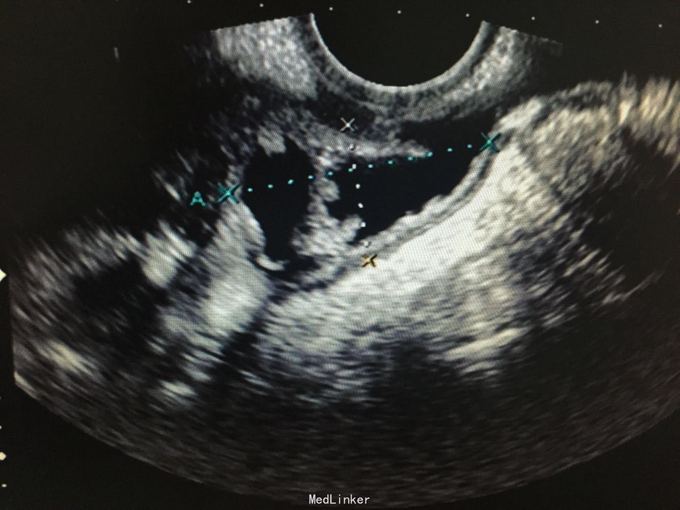

妇科查体:外阴发育正常,阴道畅,阴道断端可见输卵管,盆腔空虚。 盆腔彩超:右附件区囊性包块,建议进一步除外输卵管积水。

诊断 : 阴切术后,输卵管脱垂 治疗:阴道上窥器,见一侧输卵管脱出于阴道断端,剪开阴道顶端,打开盆底腹膜,见脱出输卵管为右侧,盆腔内输卵管积水样改变,其内见清亮液体。切除右输卵管。